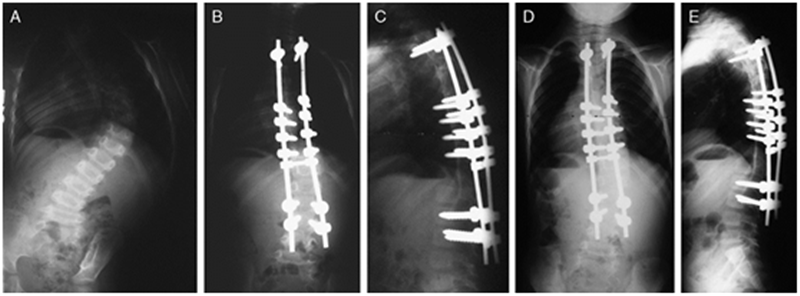

图4 A:EOS患儿术前冠状面全脊柱正位X片,左侧胸廓发育不全;B:左侧VEPTR肋骨撑开术,间接纠正脊柱畸形,以维持肺的发育

图7 McCarthy等[14]报道了38例行Shilla技术治疗的患者,随访2年以上。A:3岁婴儿特发性脊柱侧凸患儿术前正位X片;B和C为术后3月影像资料;D和E为术后2年正侧位X片